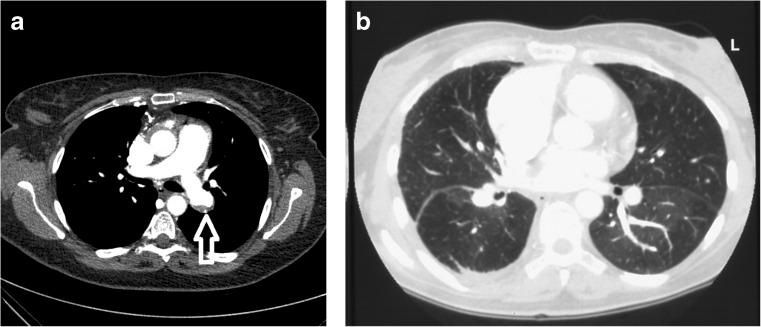

Chronic pulmonary thromboembolic disease is an important cause of severe pulmonary hypertension, and as such is associated with significant morbidity and mortality. The prognosis of this condition reflects the degree of associated right ventricular dysfunction, with predictable mortality related to the severity of the underlying pulmonary hypertension. Left untreated, the prognosis is poor. Pulmonary endarterectomy is the treatment of choice to relieve pulmonary artery obstruction in patients with chronic thromboembolic pulmonary hypertension and has been remarkably successful. Advances in surgical techniques along with the introduction of pulmonary hypertension-specific medication provide therapeutic options for the majority of patients afflicted with the disease. However, a substantial number of patients are not candidates for pulmonary endarterectomy due to either distal pulmonary vascular obstruction or significant comorbidities. Therefore, careful selection of surgical candidates in expert centres is paramount. The current review focuses on the diagnostic approach to chronic thromboembolic pulmonary hypertension and the available surgical and medical therapeutic options.